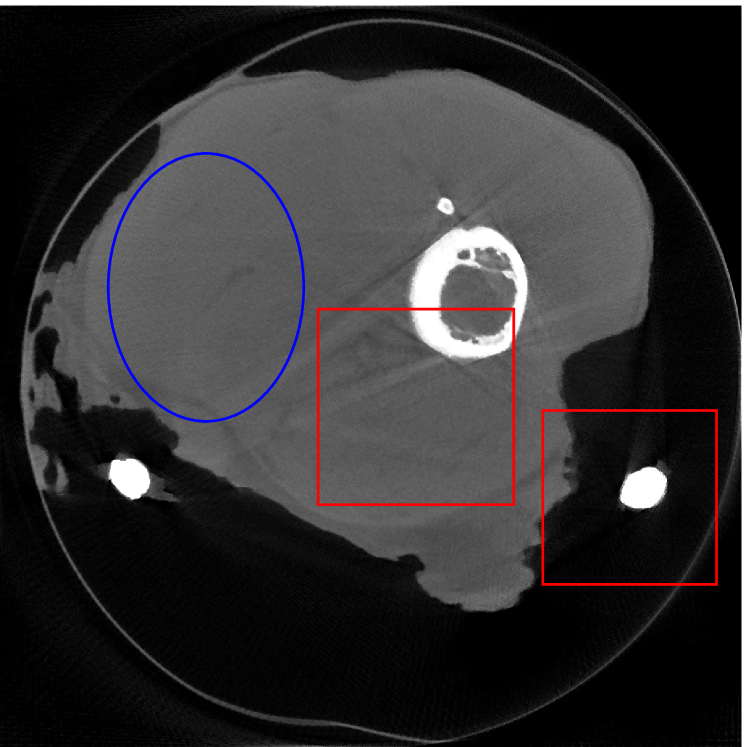

4.2 Numerical experiments: real data

We perform a CT scan of a chicken leg placed in a disposable cup (Figure 10(a)). We first scan the chicken leg without metals (Figure 10(b)) to create a reference image using FBP algorithm. Then, we place two steel thread nails on each side of the chicken leg and scan the subject again using the same scanning protocol (Figure 10(c)). The projection data is acquired from a MicroCT scanner equipped at the Division of Nuclear Technology and Applications, Institute of High Energy Physics, Chinese Academy of Sciences. The X-ray source is with 90 kV and 70 mA energy and the flat plane detector contains pixels. The scanning trajectory is a full circle with equally spaced views at per view. The physical size of each detector unit is . The distance from the X-ray source to the detector is . In order to conduct a 2D experiment, we choose the 512th row of the detector array.

Figure 11 shows the images reconstructed using FBP, the analysis model (2.12), the inpainting model (2.13) and the segmented image from the image obtained by (2.14). The reference image without metal implants are shown in Figure 11(a). All the images in this subsection are displayed within the grayscale interval . The segmented image shown in Figure 11(e) is used to estimate the weights needed in NMAR and the re-weighted JSR model.

Figure 12 shows a comparison between the reconstructed image from NMAR and the unweighted JSR model. Figure 13 shows a comparison between the reconstructed images from TV-FADM and the proposed re-weighted JSR model. Zoom-in views are provided in both Figure 12 and Figure 13 for a better visual assessment. As one can see that the reconstructed images from the unweighted JSR model and TV-FADM are less noisy than NMAR as indicated by the blue ellipse curve, whereas NMAR does a better job in preserving image features and suppressing metal artifacts. However, there are also new artifacts around the metal on the right as shown in Figure 12(d). The proposed re-weighted JSR model has best overall performance in terms of feature preservation, noise and metal artifact reduction.